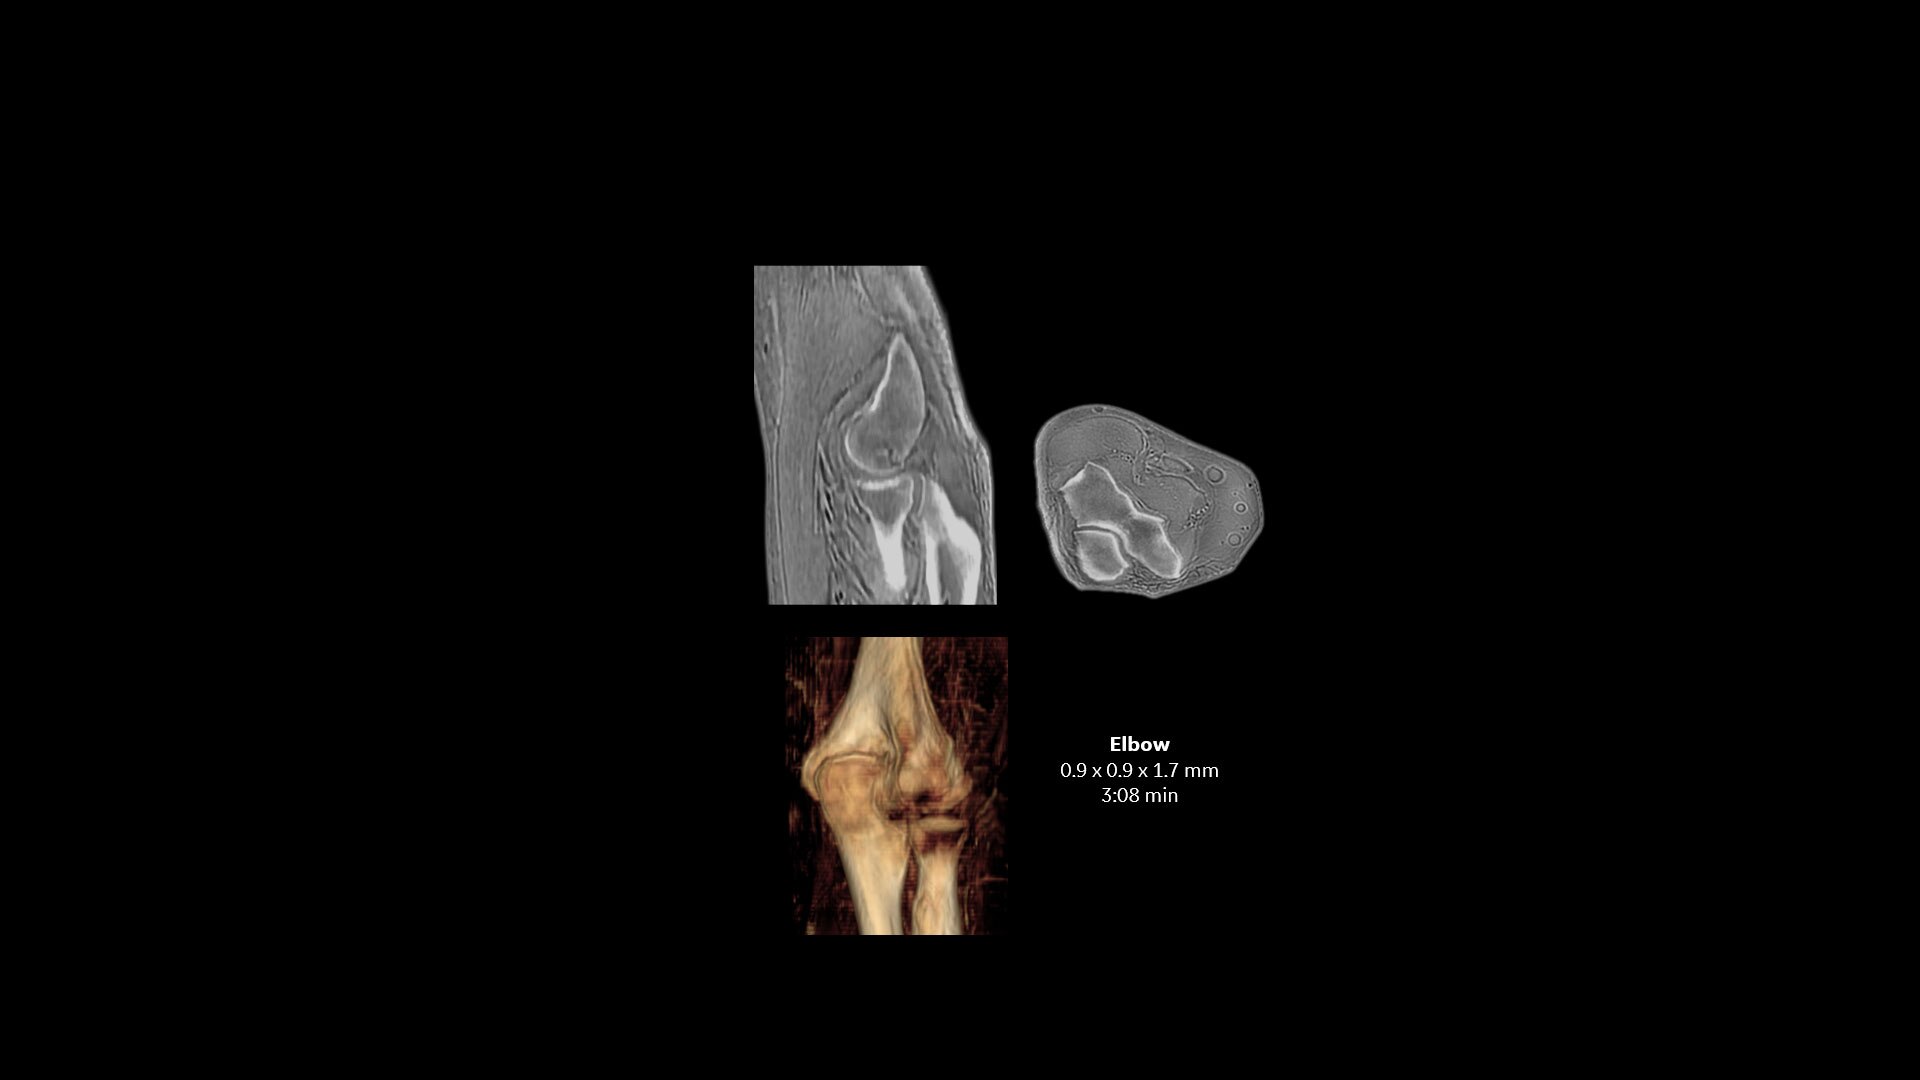

Powerful bone imaging for all anatomies

Available for all anatomies without ionizing radiation, oZTEo delivers images of bone morphology, calcification, ossification and fractures. oZTEo complements conventional MR soft tissue exams with perfect co-registration and provides 3D isotropic imaging using a radial ZTE acquisition, with inherent motion insensitivity. Use oZTEo with Volume Illumination for realistic 3D rendering.